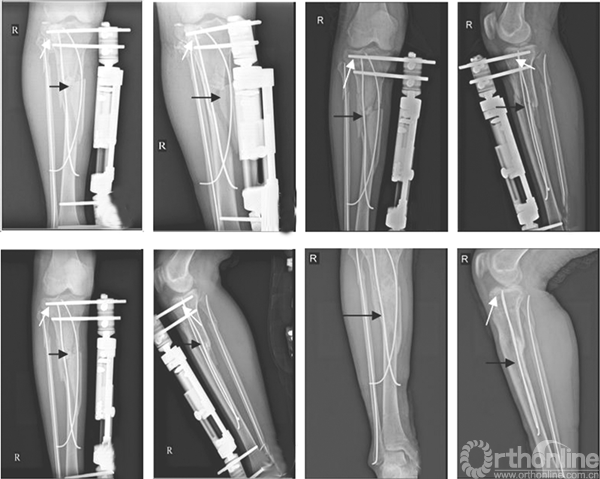

图2 右胫腓骨粉碎性骨折术后[A、B:患者髓内髓外系统联合固定术后1 周X 线,白色箭头示胫骨平台塌陷位置借助TENs复位后;黑色箭头示胫骨干粉碎性骨折复位术后;C、D:术后4 周,胫骨平台关节面基本恢复(白箭头所示),胫骨干少量骨痂出现(黑箭头所示);E、F:术后8 周,平台骨折线模糊,胫骨干大量骨痂出现;G、H:术后半年,外固定拆除后,平台关节面恢复良好,胫骨干骨折达骨性愈合。